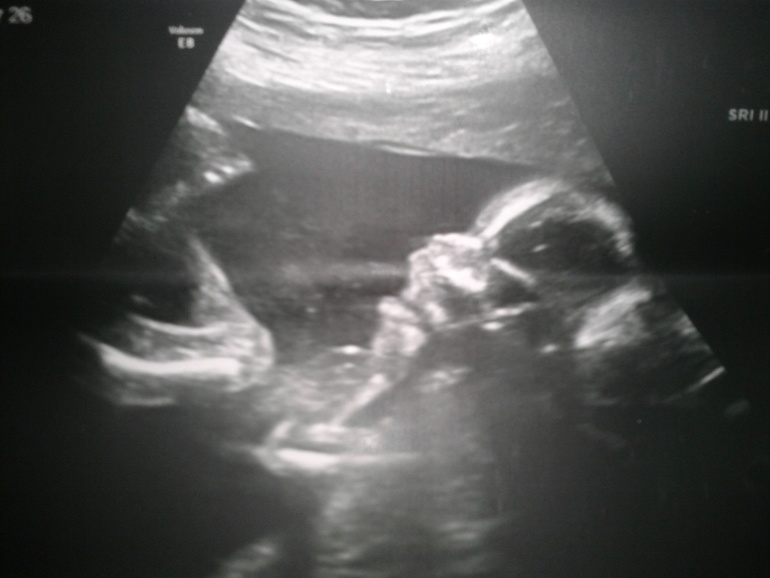

вот и мой красавчик))носик задрал,улыбается))глазки только в тени,забился блин в угол головой, и опять обломал меня с 3д фоткой(

а тут мы руку под подбородок деловито подставили, вторую под голову,смотрим "по сторонам,понимаете ли))"